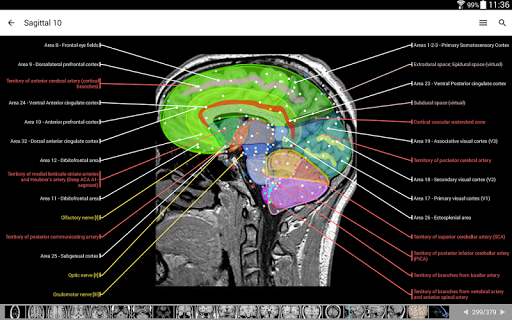

IMAIOS e-Anatomy adalah atlas anatomi manusia untuk dokter, ahli radiologi, mahasiswa kedokteran, dan teknisi radiologi. Dapatkan cuplikan lebih dari 26.000 gambar medis dan anatomi secara gratis sebelum berlangganan atlas anatomi manusia terperinci kami.

e-Anatomy didasarkan pada atlas daring IMAIOS e-Anatomy yang telah memenangkan penghargaan. Bawalah referensi anatomi manusia terlengkap, ke mana pun Anda pergi, di perangkat seluler atau tablet Anda.

e-Anatomy memiliki lebih dari 26.000 gambar yang berisi serangkaian gambar dalam tampilan aksial, koronal, dan sagital serta radiografi, angiografi, gambar diseksi, bagan anatomi, dan ilustrasi. Semua gambar medis diberi label dengan cermat, lebih dari 967.000 label tersedia dalam 12 bahasa termasuk Terminologia Anatomica Latin.

- Gulir set gambar dengan menyeret jari Anda

- Perbesar dan perkecil

- Ketuk label untuk menampilkan struktur anatomi

- Pilih label anatomi berdasarkan kategori